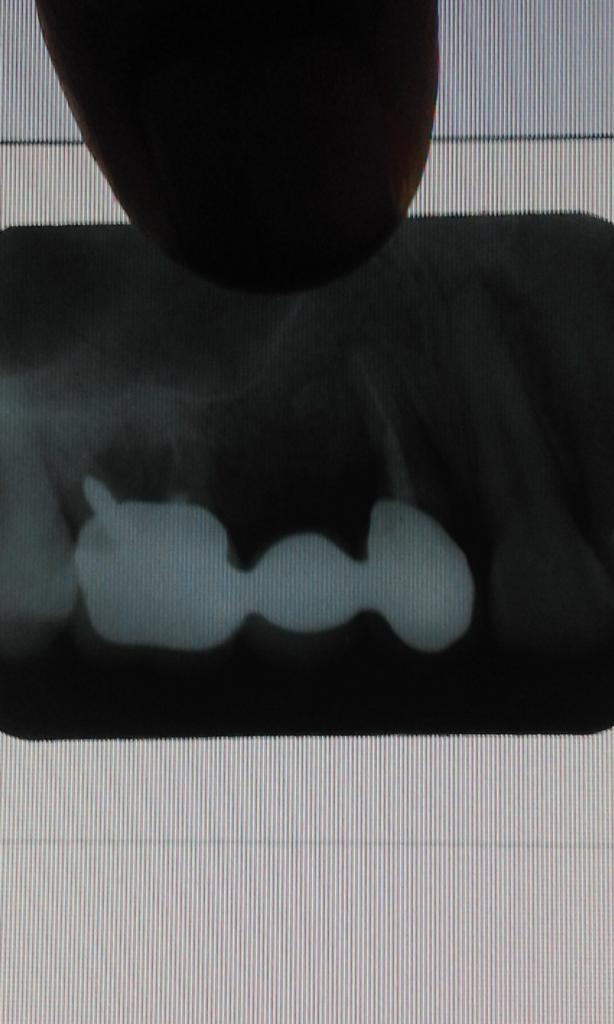

Вложение 10240185

Вот такая штука))

Красота красотой ,но тройка не выдержит мост ( судя по состоянию тканей между тройкой и двойкой).

Тройку видимо прийдется удалить, желательно сделать съемный бюгельный протез. Отсроченная остеопластика.